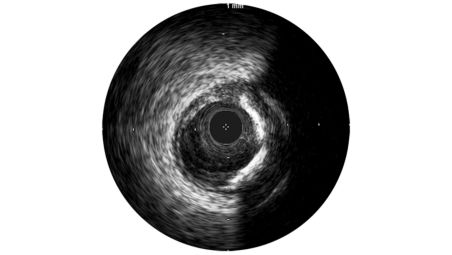

A 45 MHz frequency produces crisp, sharp imaging for dependable interpretation and assessment of vessel morphology.